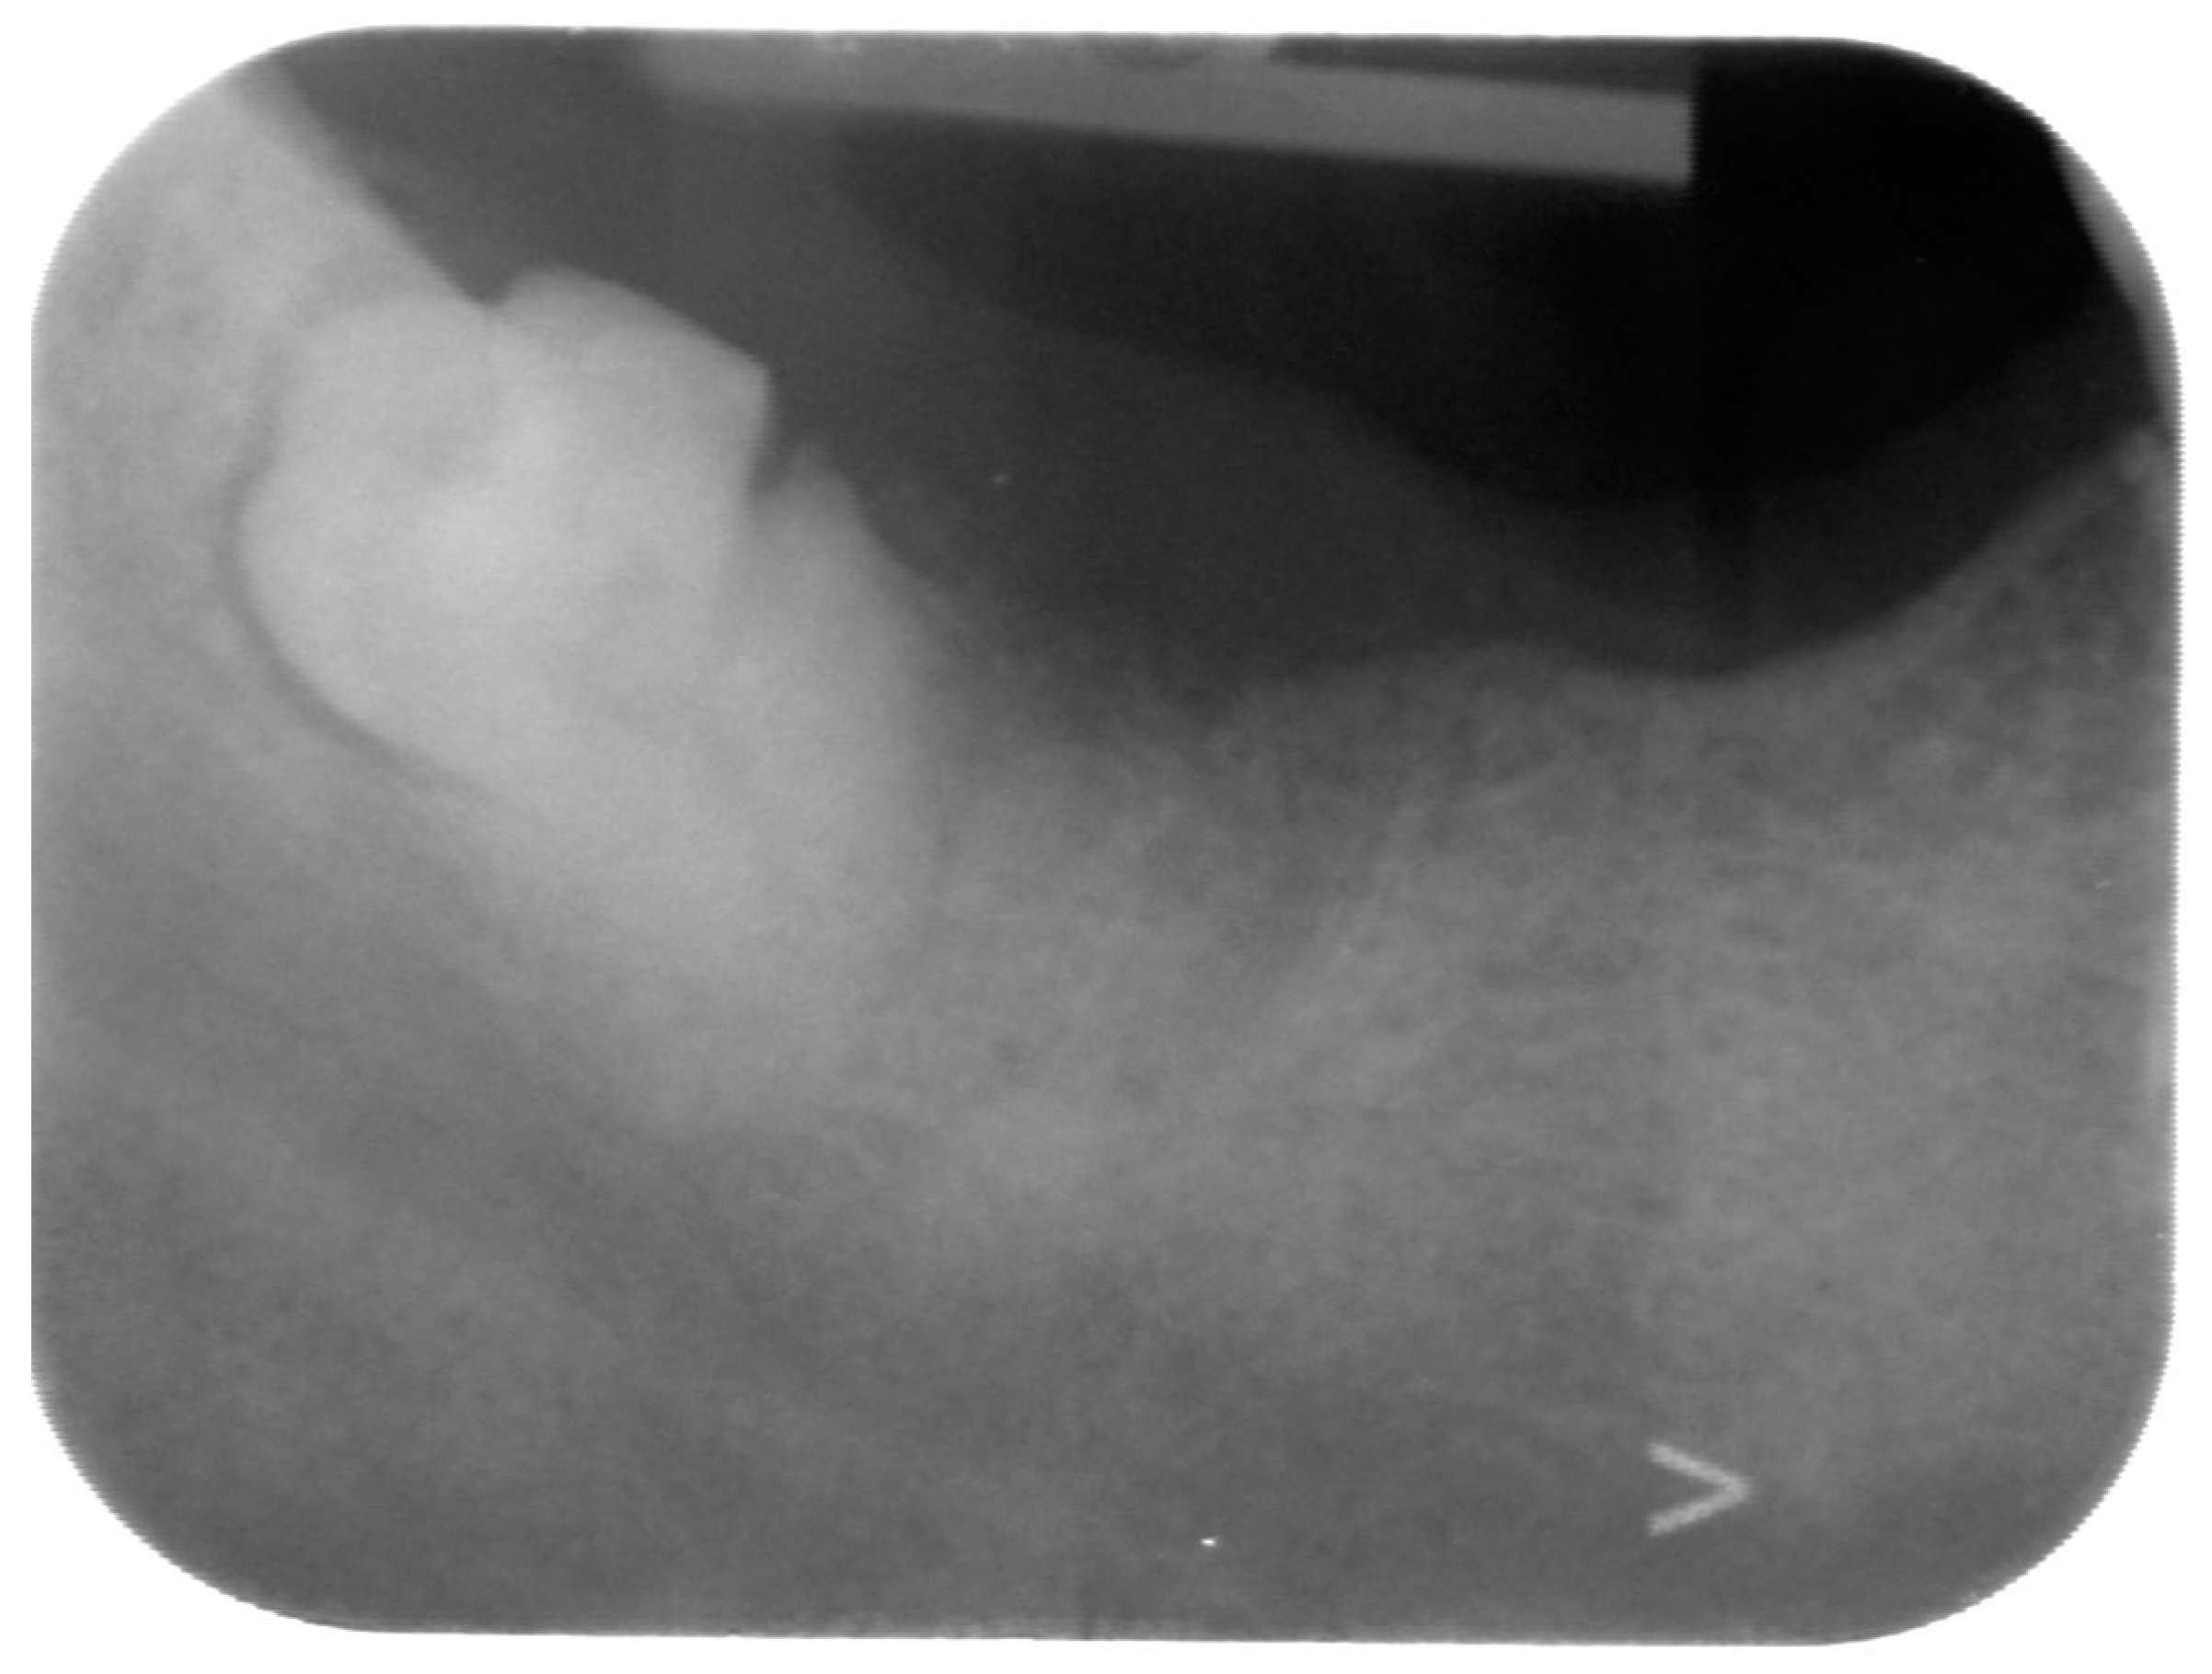

The first-level radiographic examination that was performed was an intra-oral radiograph, suspecting root remnants that were not removed following the punches (Figure 1). On RX, root remnants of teeth in lower right side were absent, but an impacted wisdom tooth was observed.

Figure 1.

Intra oral X-ray showing a partly impacted fractured lower right wisdom tooth.